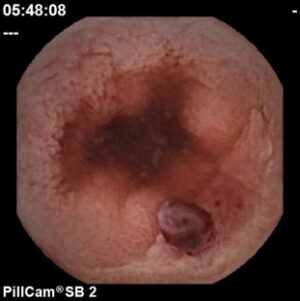

Estenose ulcerada em Doença de Crohn

Hospital Senhora da Oliveira (Guimarães)